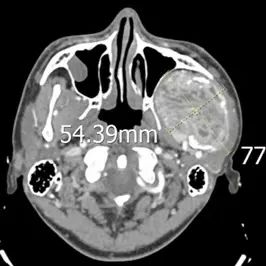

来自偏远地区的18岁的藏族小伙才让多杰(化名),近一年来因右侧面部逐渐肿胀增大,且伴有疼痛不适,在当地医院就诊,检查发现他的右侧面部有一约7cmx9cm的肿物,活检穿刺后病理结果提示为“梭形细胞瘤”,结合免疫组化染色结果,多考虑孤立性纤维性肿瘤(孤立性纤维瘤是一种罕见的低度恶性肿瘤)。经朋友推荐,才让多杰在哥哥的陪同下来到了联勤保障部队第940医院颌面外科就诊。在完善相关检查后,才让多杰的病情得到了进一步确诊,进入了紧张而有序的手术准备阶段。

由于才让多杰的肿瘤主要在颅底,已经侵犯到部分下颌骨、面神经和周围的肌肉组织,为达到较好的手术效果,颌面外科马东洋主任组织全科人员对才让多杰的病情进行分析讨论,认为患者肿瘤位置特殊,周围重要解剖结构多,如何最大程度规避风险,降低手术并发症,对肿瘤扩大切除术后造成的下颌骨部分缺失,使用何种方法进行同期修复,是本次手术中需要解决的重要问题。经过讨论,专家团队决定采用数字化3D打印、CT导航和虚拟手术技术对才让多杰的肿瘤位置、大小及周围重要解剖结构进行详细评估,同时对切除部分下颌骨后使用带血管蒂腓骨移植修复方案进行模拟,以达到精准的修复效果。